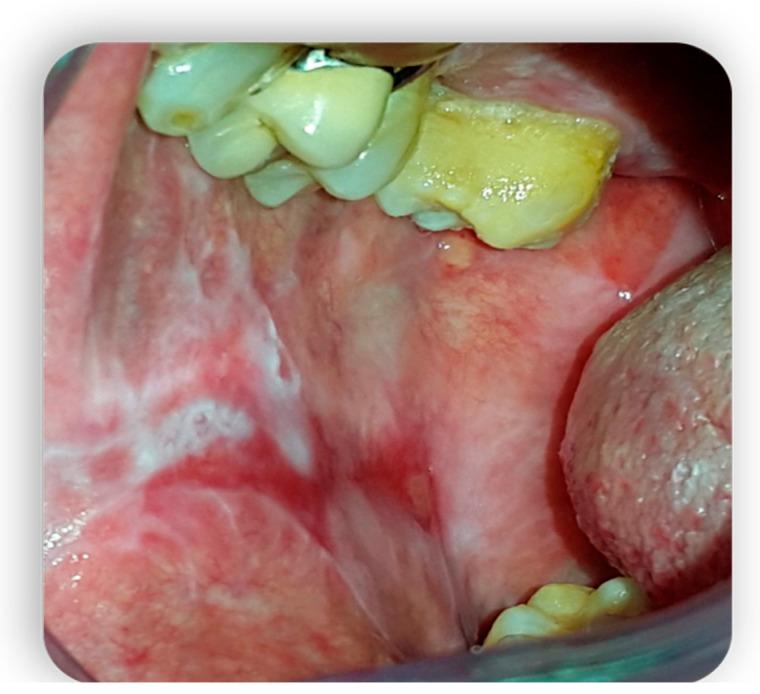

Graft-versus-host disease (GVHD) is a complication of hematopoietic stem cell transplantation (HSCT). GVHD may also develop following solid transplants or blood transfusions if white blood cells are transferred. GVHD affects multiple organs, including the oral tissues. This pictorial review provides a background of GVHD to dental practitioners, describes the most common oral manifestations of GVHD, and highlights the main treatment modifications needed to deliver dental care to patients with GVHD. A narrative review enriched with clinical data was performed by searching the scientific literature for all articles regarding GVHD and oral manifestations/therapies. All articles without exclusion criteria, except animal tests, were included in the above review. Acute GVHD may manifest in the oral mucosa; however, it often develops immediately following HSCT when routine dental treatment is postponed. Chronic GVHD may manifest in the oral mucosa, the salivary glands, and the musculoskeletal compartment. It may indirectly affect the teeth and the oral flora, putting the patient at risk for infections. Importantly, GVHD poses an increased risk for oral cancer. GVHD has a wide range of oral manifestations, some of which may affect dental treatment.